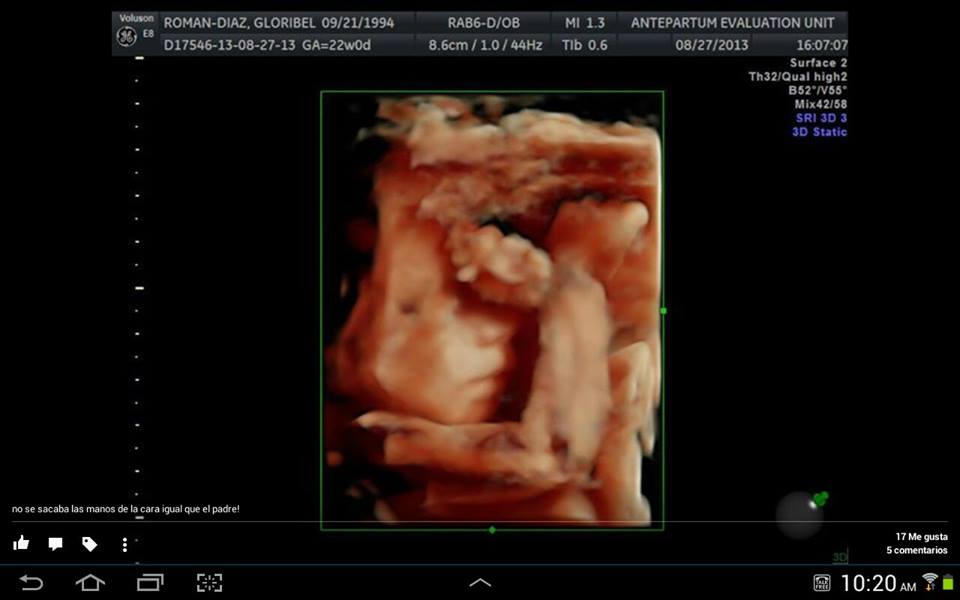

Gloribel y Jairol nos presentan a su bebé con 22 semanas de gestación, se llamará Jairome M.